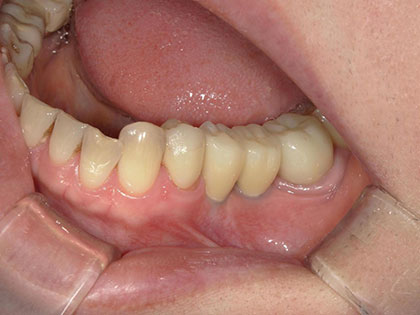

• 初診時の写真がこちら

• インプラント術前1